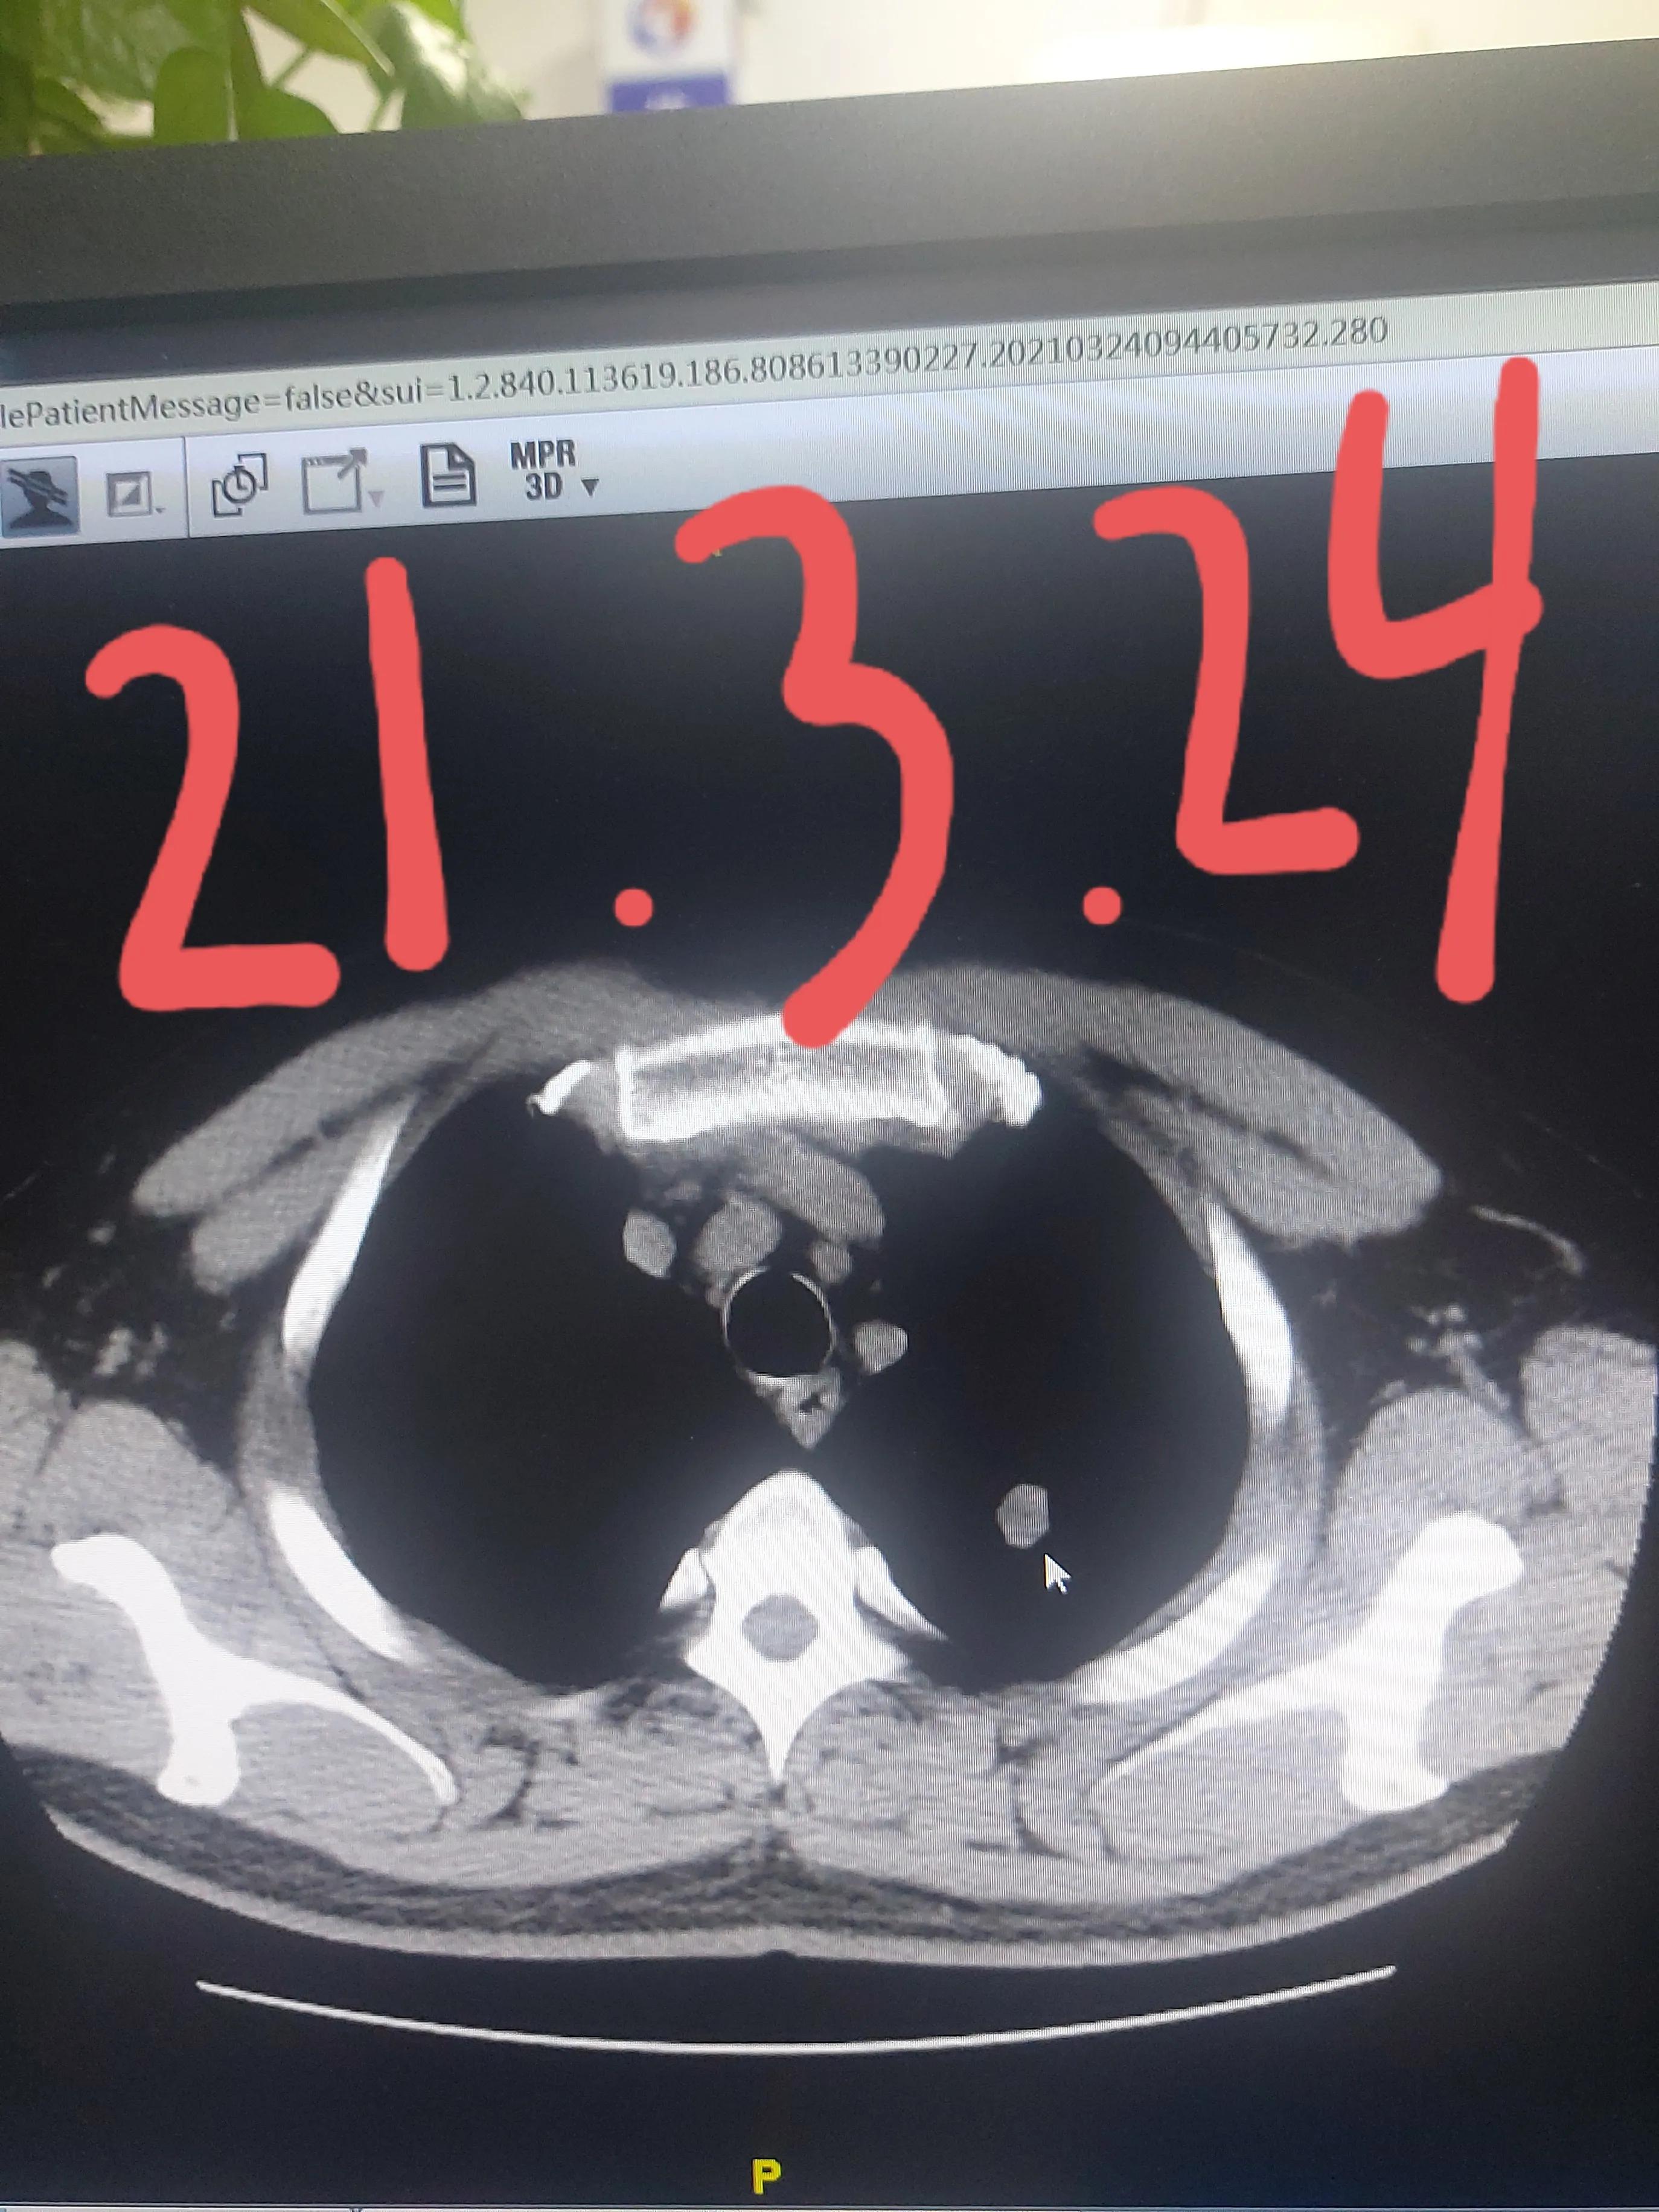

张先生今年44岁,一个月之前因为咳嗽去呼吸科就诊拍胸部CT,发现了左上肺有一个实性的结节,得到这个结果,本人和家属都特别紧张,怕是有肺癌的可能性。家属托到熟人找到了我,我看过他的片子,告诉他不要担心,这个结节现在不需要直接手术,先听我的,抗炎治疗之后再复查,如果结节变小了,就不需要手术了,如果还是这样,再手术也来得及。

家属听从了我的安排,我给安排好了抗炎治疗,经过了一个疗程的治疗,距离上次一个月复查了胸部CT,果然这个结节比之前变小,并且出现了空洞,种种迹象表明这是一个良性的结节,我告诉他现在更不需要紧张了,目前不考虑是肺癌,定期再来复查就可以了,肯定不需要手术。